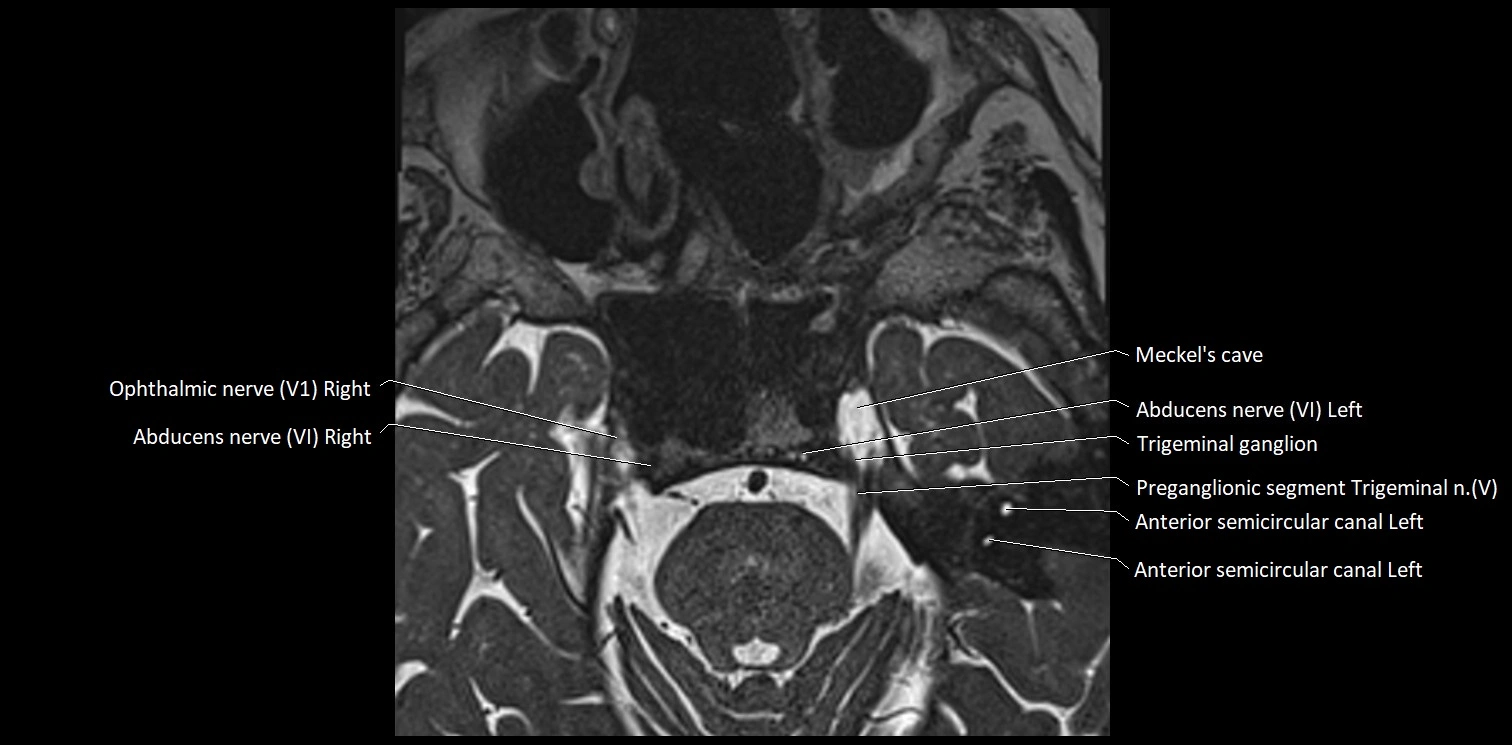

MRI Appearance

• The abducens nerve is a small, thin, linear structure

• Best visualized on high-resolution T2-weighted 3D MRI sequences (e.g., FIESTA or CISS)

• Seen as a hypointense (dark) line running from the brainstem at the pontomedullary junction, traversing the prepontine cistern, and entering Dorello’s canal under the petrosphenoidal ligament, then into the cavernous sinus, and finally the orbit

• May be challenging to visualize in standard MRI due to its small size

• Pathology may be inferred by absence, displacement, or enhancement of the nerve

MRI images

image